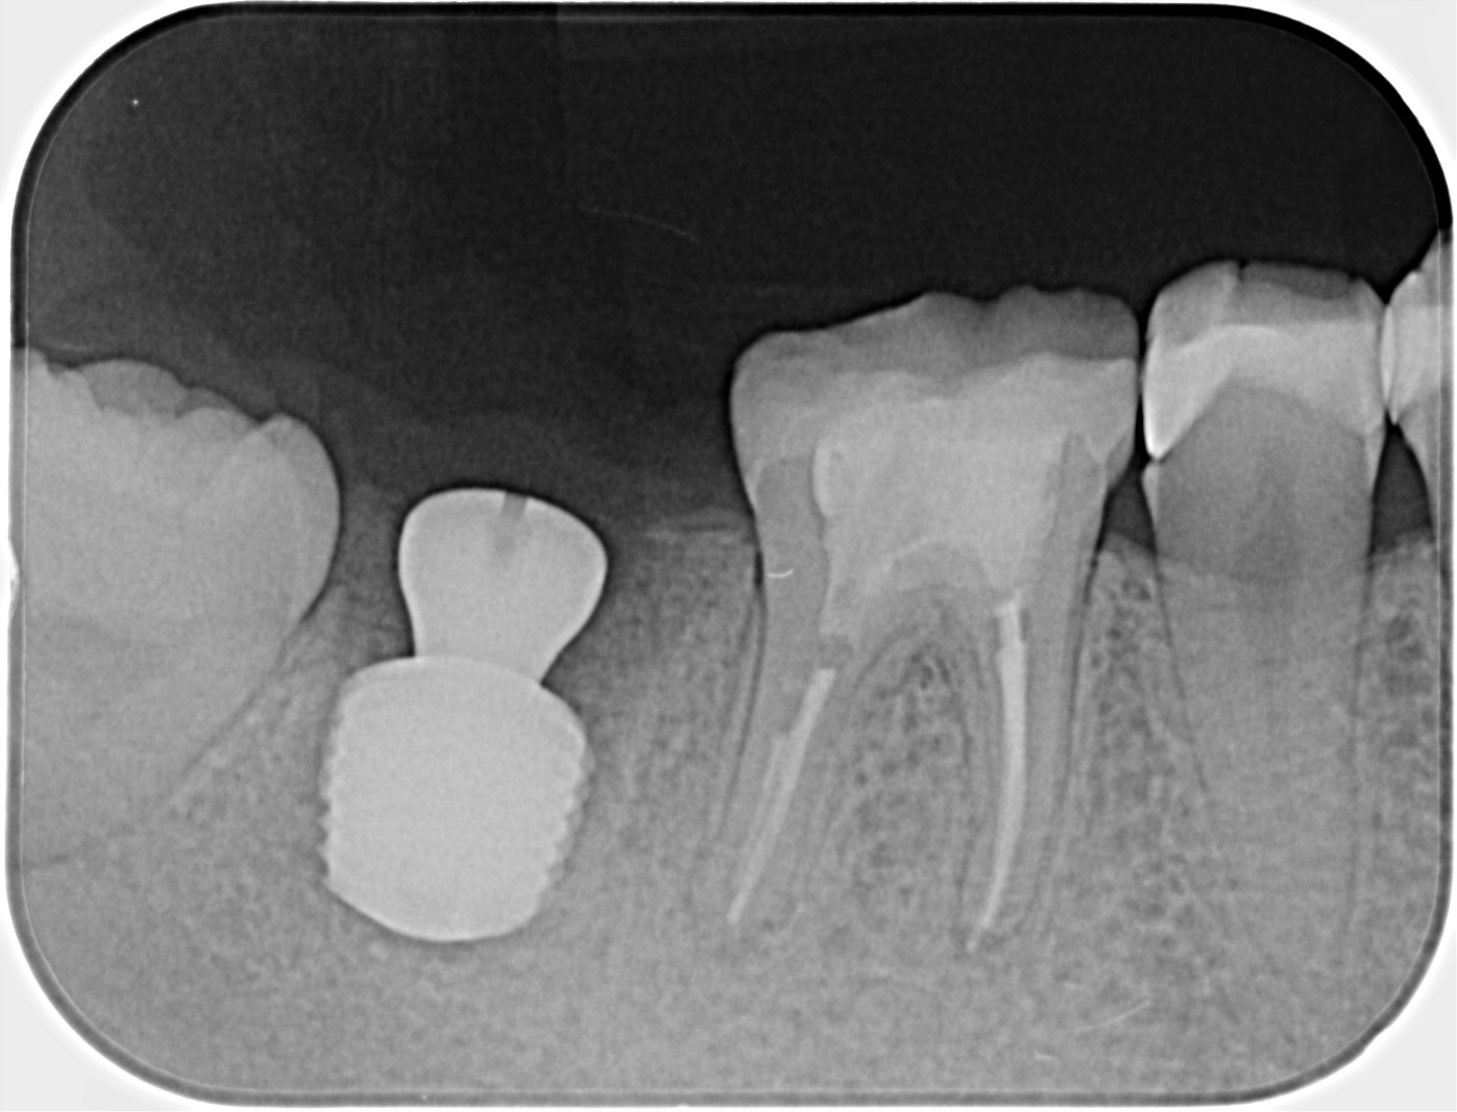

30代、女性、右下に違和感があることを健診中に申され、インプラント治療を行いました。

| 患者様の主訴 | 右下に違和感がある |

| 診断結果 | 右下7番歯根破折 |

| 治療内容 | 抜歯即時インプラント |

| 治療期間 | 8週間 |

| 治療費用 | ¥539,000(税込) |